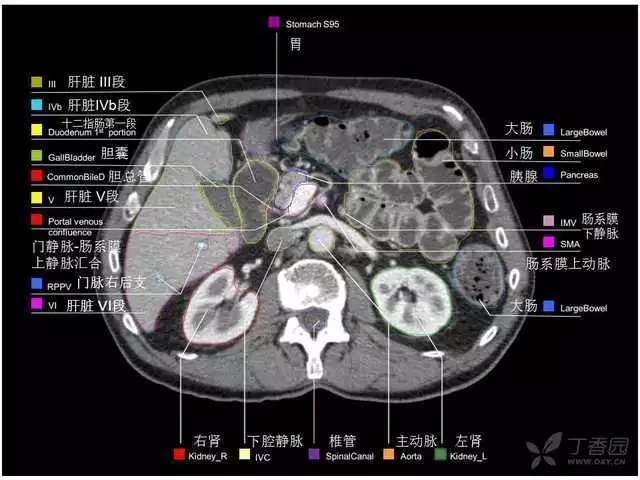

腹部肝脏高清CT断层的图谱

全腹部高清CT图谱,淋巴结彩色图谱,血管解剖图谱大汇总!

超声肝脏分叶及分段

肝脏分段和基本解剖学标志